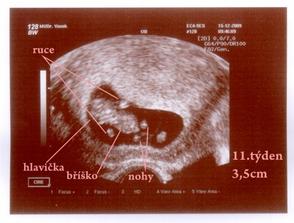

Náš malý Velký Zázrak - na světě II.

Jakub roste jako z vody 🙂 tak hlavně ať je pořád zdravý a má se dál k světu.